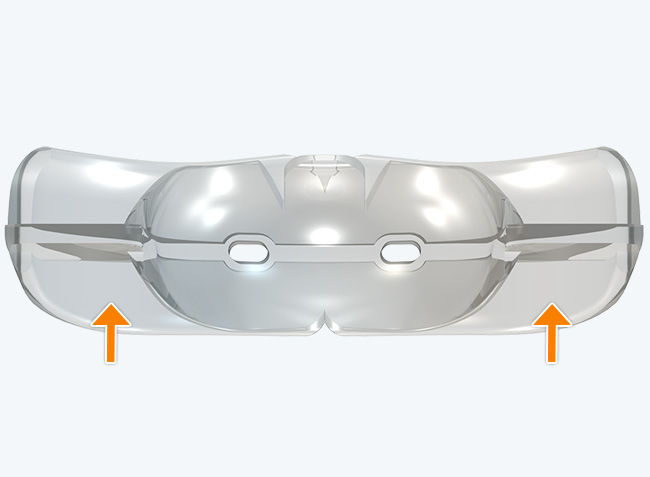

The TMJ Appliance®, which does not require any special fitting, is designed to act as an initial diagnostic and treatment tool for TMJ disorder. It works by decompressing the temporomandibular joint (TMJ), helps to correct mouth breathing and tongue posture habits, as well as limits bruxing. The TMJ Appliance® achieves TMJ disorder symptom relief immediately by alleviating pressure on the TMJ and relaxes the muscles around the jaw and neck.